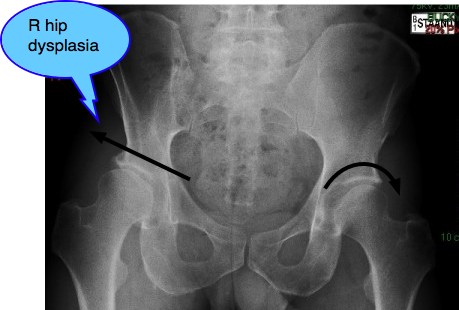

Mr P, a 52-year old man presented recently with right hip and groin pain, beginning about three years previously. Despite various medical treatments, it was clear that the condition was worsening. Putting on shoes and socks was becoming difficult. Walking was painful.

Interestingly, he knew the answer to one important question, mostly never known. He remembers his mother telling him that during her pregnancy that he lay in the Transverse position. Both the transverse position, and the breech presentation are known to be associated with a much higher incidence of Developmental Hip Dysplasia.

Mr P's right hip: Hip Dysplasia

Note the sloping acetabulum, an unroofed one-third of the femoral head, the shallow socket and the beginnings of arthritis at the superior labral margin. Progressive hip arthritis.